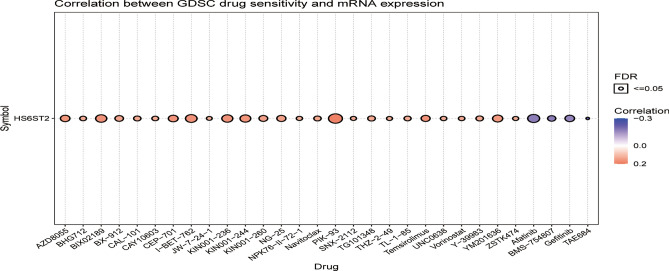

The correlation between HS6ST2 expression and predicted treatment sensitivity

Analysis via the GDSC database disclosed a substantial association between HS6ST2 mRNA expression and predicted response to 78 anticancer treatments (Supplementary Table S1). The expression of HS6ST2 was positively linked with drug sensitivity in most malignancies, such as PIK-93, I-BET-762, BIX02189, KIN001-236, CEP-701, KIN001-244, AZD8055, YM201636, NG-25, and KIN001-260 (Fig. 11). In contrast, there was an inverse relationship between HS6ST2 expression and sensitivity to four small molecules and drugs: afatinib, BMS-754807, TAE684, and gefitinib. According to these results, HS6ST2 may be a possible therapeutic target for malignancies.

Despite the emergence of newer technologies and tailored therapeutics, resistance to drugs remains a major problem for researchers in the laboratory and clinic, and new drug resistance-combating strategies have been developed, such as restoring the function of tumor suppressor genes42 and RNA interference43. We determined the correlation of HS6ST2 with the IC50 values of over 750 anti-cancer medications. The data showed that increased HS6ST2 expression was correlated with reduced sensitivity to numerous drugs, indicating its probable participation in medication resistance; in contrast, increase HS6ST2 expression was correlated with increased sensitivity to afatinib, BMS754807, gefitinib, and TAE684. This discovery suggests that modulating the expression of HS6ST2 may be a strategy for enhancing anticancer drug efficacy. Finally, our enrichment studies implied that HS6ST2 may influence the pathophysiology and/or etiology of cancer by functioning in RNA processing, gene silencing, epithelial cell differentiation, the cytosolic DNA sensing pathway, antigen processing and presentation, and/or drug metabolism. According to these results, HS6ST2 may regulate tumor development via these mechanisms. In addition, a number of experiments were conducted to evaluate the expression of HS6ST2 in LUAD tissues. HS6ST2 was increased in LUAD tissues compared to nearby normal tissues.